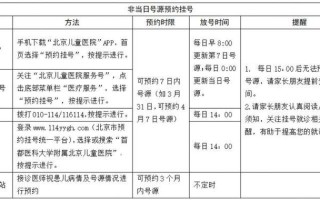

儿童鼓膜置管手术图解

什么是鼓膜置管手术?

鼓膜置管手术是一种在全身麻醉下进行的小型门诊手术,医生会在孩子的鼓膜上切一个小口,然后置入一个微小的中空管(通气管),这个管子像一个“微型通风口”,可以:

(图片来源网络,侵删)

- 引流中耳积液: 将中耳内积聚的液体(如胶耳)引流出来。

- 平衡气压: 让空气能够进入中耳,与外界气压保持平衡,从而改善听力,预防中耳炎反复发作。

这就像给堵塞的耳朵“开一扇窗户”,让耳朵恢复正常功能。

手术步骤详解

整个手术过程非常迅速,通常只需要10-15分钟。

麻醉

- 方式: 儿童通常采用全身麻醉,确保孩子在手术过程中完全无痛、无恐惧,并能保持安静不动。

- 图示: 孩子会睡过去,医生会进行术前准备。

进入手术区域

- 方式: 医生会使用一个叫做耳内镜的细长、带摄像头和光源的仪器,轻轻伸入孩子的外耳道。

- 图示: 耳内镜能将鼓膜的放大图像实时显示在屏幕上,让医生看得非常清楚。

切开鼓膜

- 方式: 医生会用一个非常精细的器械(如小刀或激光),在鼓膜的前下象限安全地切一个极小的切口(通常只有2-3毫米)。

- 图示: 鼓膜被切开,中耳内积存的黄色或粘稠液体(胶耳)会立即流出。

置入通气管

- 方式: 医生会用一个细小的器械,将一个预先准备好的通气管(也叫“鼓膜通气管”或“Grommet”)放入鼓膜的小切口中。

- 图示: 通气管放置好后,会像一个小塞子一样固定在鼓膜上,一端在中耳内,一端在外耳道。

手术完成

- 方式: 通气管放置到位后,医生会退出耳内镜,手术结束。

- 图示: 手术完成后,鼓膜上的通气管清晰可见,它允许空气和液体自由通过,从而解决中耳问题。

(图片来源网络,侵删)